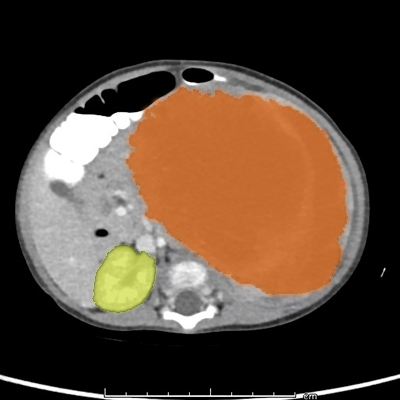

Each year in the UK, over 100 infants under the age of one are diagnosed with rare cancerous tumours in their soft tissues. One of these soft tissue cancers, known as congenital mesoblastic nephroma (CMN), is the most common kidney tumor diagnosed in early infancy. Occasionally spotted as a lump in utero during an ultrasound scan, these tumours are diagnosed definitively after birth. Treatment involves surgical removal of the tumour and sometimes chemotherapy, both of which can damage surrounding tissues at a critical time in life.

In a new study using samples from archives in Germany and Great Ormond Street Hospital, London, scientists from the Wellcome Sanger Institute and their collaborators sequenced the whole genomes and transcriptomes* of 17 CMN tumours, and extended their findings to a total of 350 cases, including CMN and five related soft tissue tumour types: infantile fibrosarcoma (IFS), nephroblastomatosis, Wilms tumour, malignant rhabdoid tumour and clear cell sarcoma of the kidney.